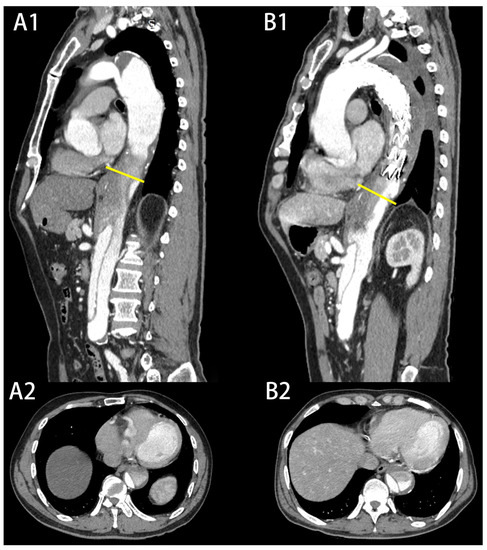

| Maximum descending aortic diameter (mm), mean ± SD | 41.3 ± 4.5 | 37.5 ± 3.0 | <0.001 |

| T10 | Expanded group | 40.1 ± 4.2 | 44.0 ± 4.0 |

| Non-expanded group | 36.3 ± 3.8 | 36.1 ± 4.4 | |

| T12 | Expanded group | 35.8 ± 3.7 | 40.6 ± 5.3 |

| Non-expanded group | 34.4 ± 2.8 | 35.1 ± 3.2 | |